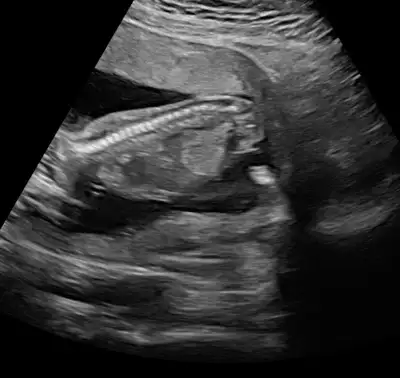

Yüz üstü olduğunu nerden anlıyorsun canım. Ben hiçbirşey anlamıyorum ya. Doktor da demiyor şu pozisyonda becak arası şu organ var eli şu kolu şu. Son gittiğimdeki doktor söyledi sadece o da 2 dakika baktı bakmadı kalktım.Ay hadi ya tutmayan bi seni gördüm bakgerçi banada telefonlar geliyor millet rüyasında hamile oldumu oğlum olduğunu görüyormuş daha bilen yok ailelerden başka hamile oldumu doğurunca yayınlıcam bende 20.hafta detaylıyı bekliyorum değişmezde çocuk yüzüstüydü hep bide sırt üstü görek kız olduğunu

Cnm ayna gibi usg hep yüsütüydü asla kıpırdamadı neden dedim uyuyor dedi banada hiç bilgi vermez vermedi direk kız dedi kesin mi dedim kesin dedi, sinir oldum insan bir uyandırır zorlar falan 10dk bakmadı ama fotoda kız gibi yinede 20yi bekliyorum düzgün göreyim anlatsın bi doktorda ya bak fotolarıma, şu son fotoda bacak arası gözüküyor ama emin olamıyorum çünkü göstermedi doktor şurası şu diyeYüz üstü olduğunu nerden anlıyorsun canım. Ben hiçbirşey anlamıyorum ya. Doktor da demiyor şu pozisyonda becak arası şu organ var eli şu kolu şu. Son gittiğimdeki doktor söyledi sadece o da 2 dakika baktı bakmadı kalktım.

Hngisiymiş pipiKizlar beni bile tereddutte biraktirdiniz cinsiyet konusunda aksam aksam ultrasyon resmine baktimdegisirmi bilemiyorum artik ayrintiliya daha var doktor pipisi bu dedi sag tarafa bakin

Kiz kafasi obur taraftabu alt bolumu bacak arasiymis orasi degisirmi dedim bak simdi burda gorunen degisirmi dedi. Bilemedim artik